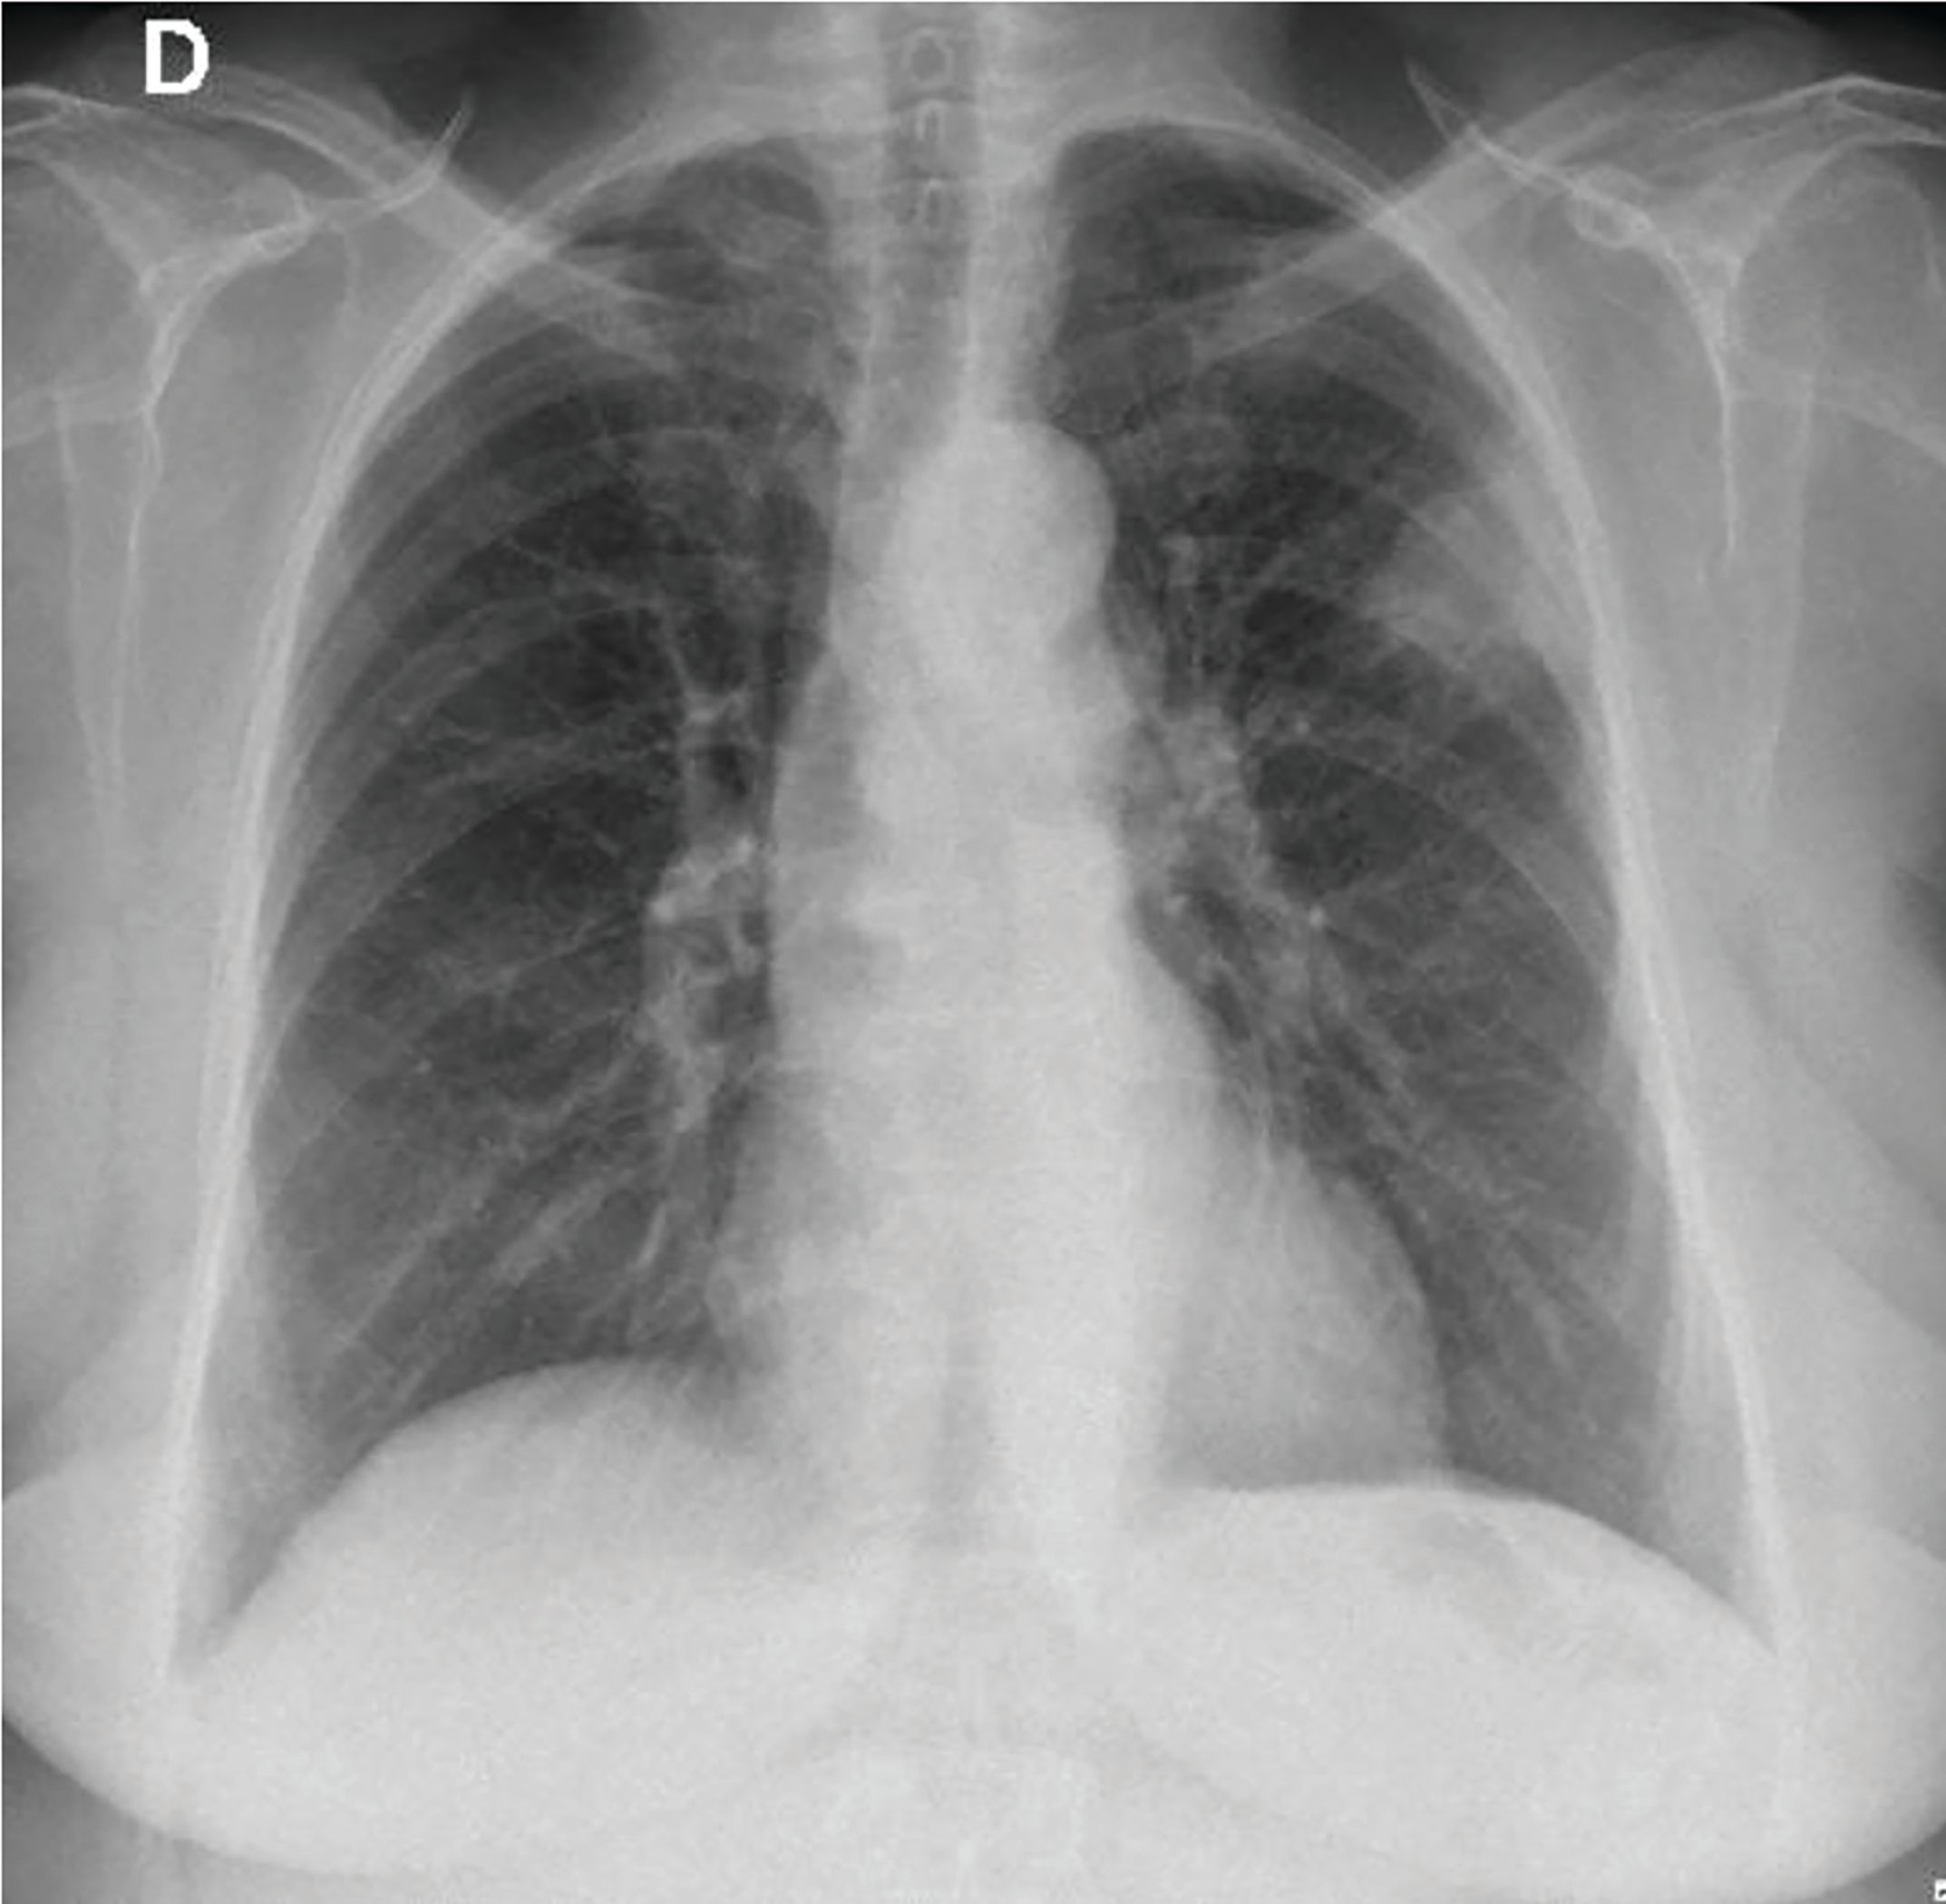

In an asymptomatic 77-year-old woman, former 55 pack-years smoker, a routine X-ray showed a 45-mm superior left lobe lesion (Figure 1). A chest CT scan confirmed a 36-mm superior left lobe lesion and an aortic-pulmonary lymph node enlargement measuring 42 mm, suspicious for neoplasia (Figure 2). A PET-CT scan showed an elevated uptake in the primary lesion, in the aortic-pulmonary lymph node, and in the left hilar lymph node with a standardized uptake value – 40 and 4.3, respectively (Figure 3).

Figure 1. X-ray and the left superior lesion.